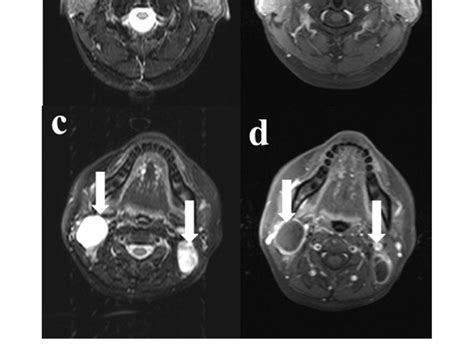

Neck CT; necrotic lymph nodes compressing the trachea. Download